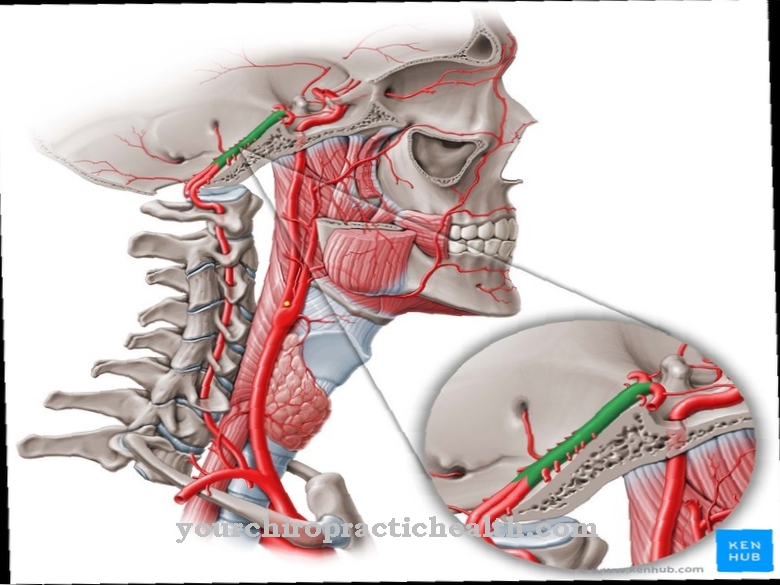

Особенности и диагностика левостороннего кровотока